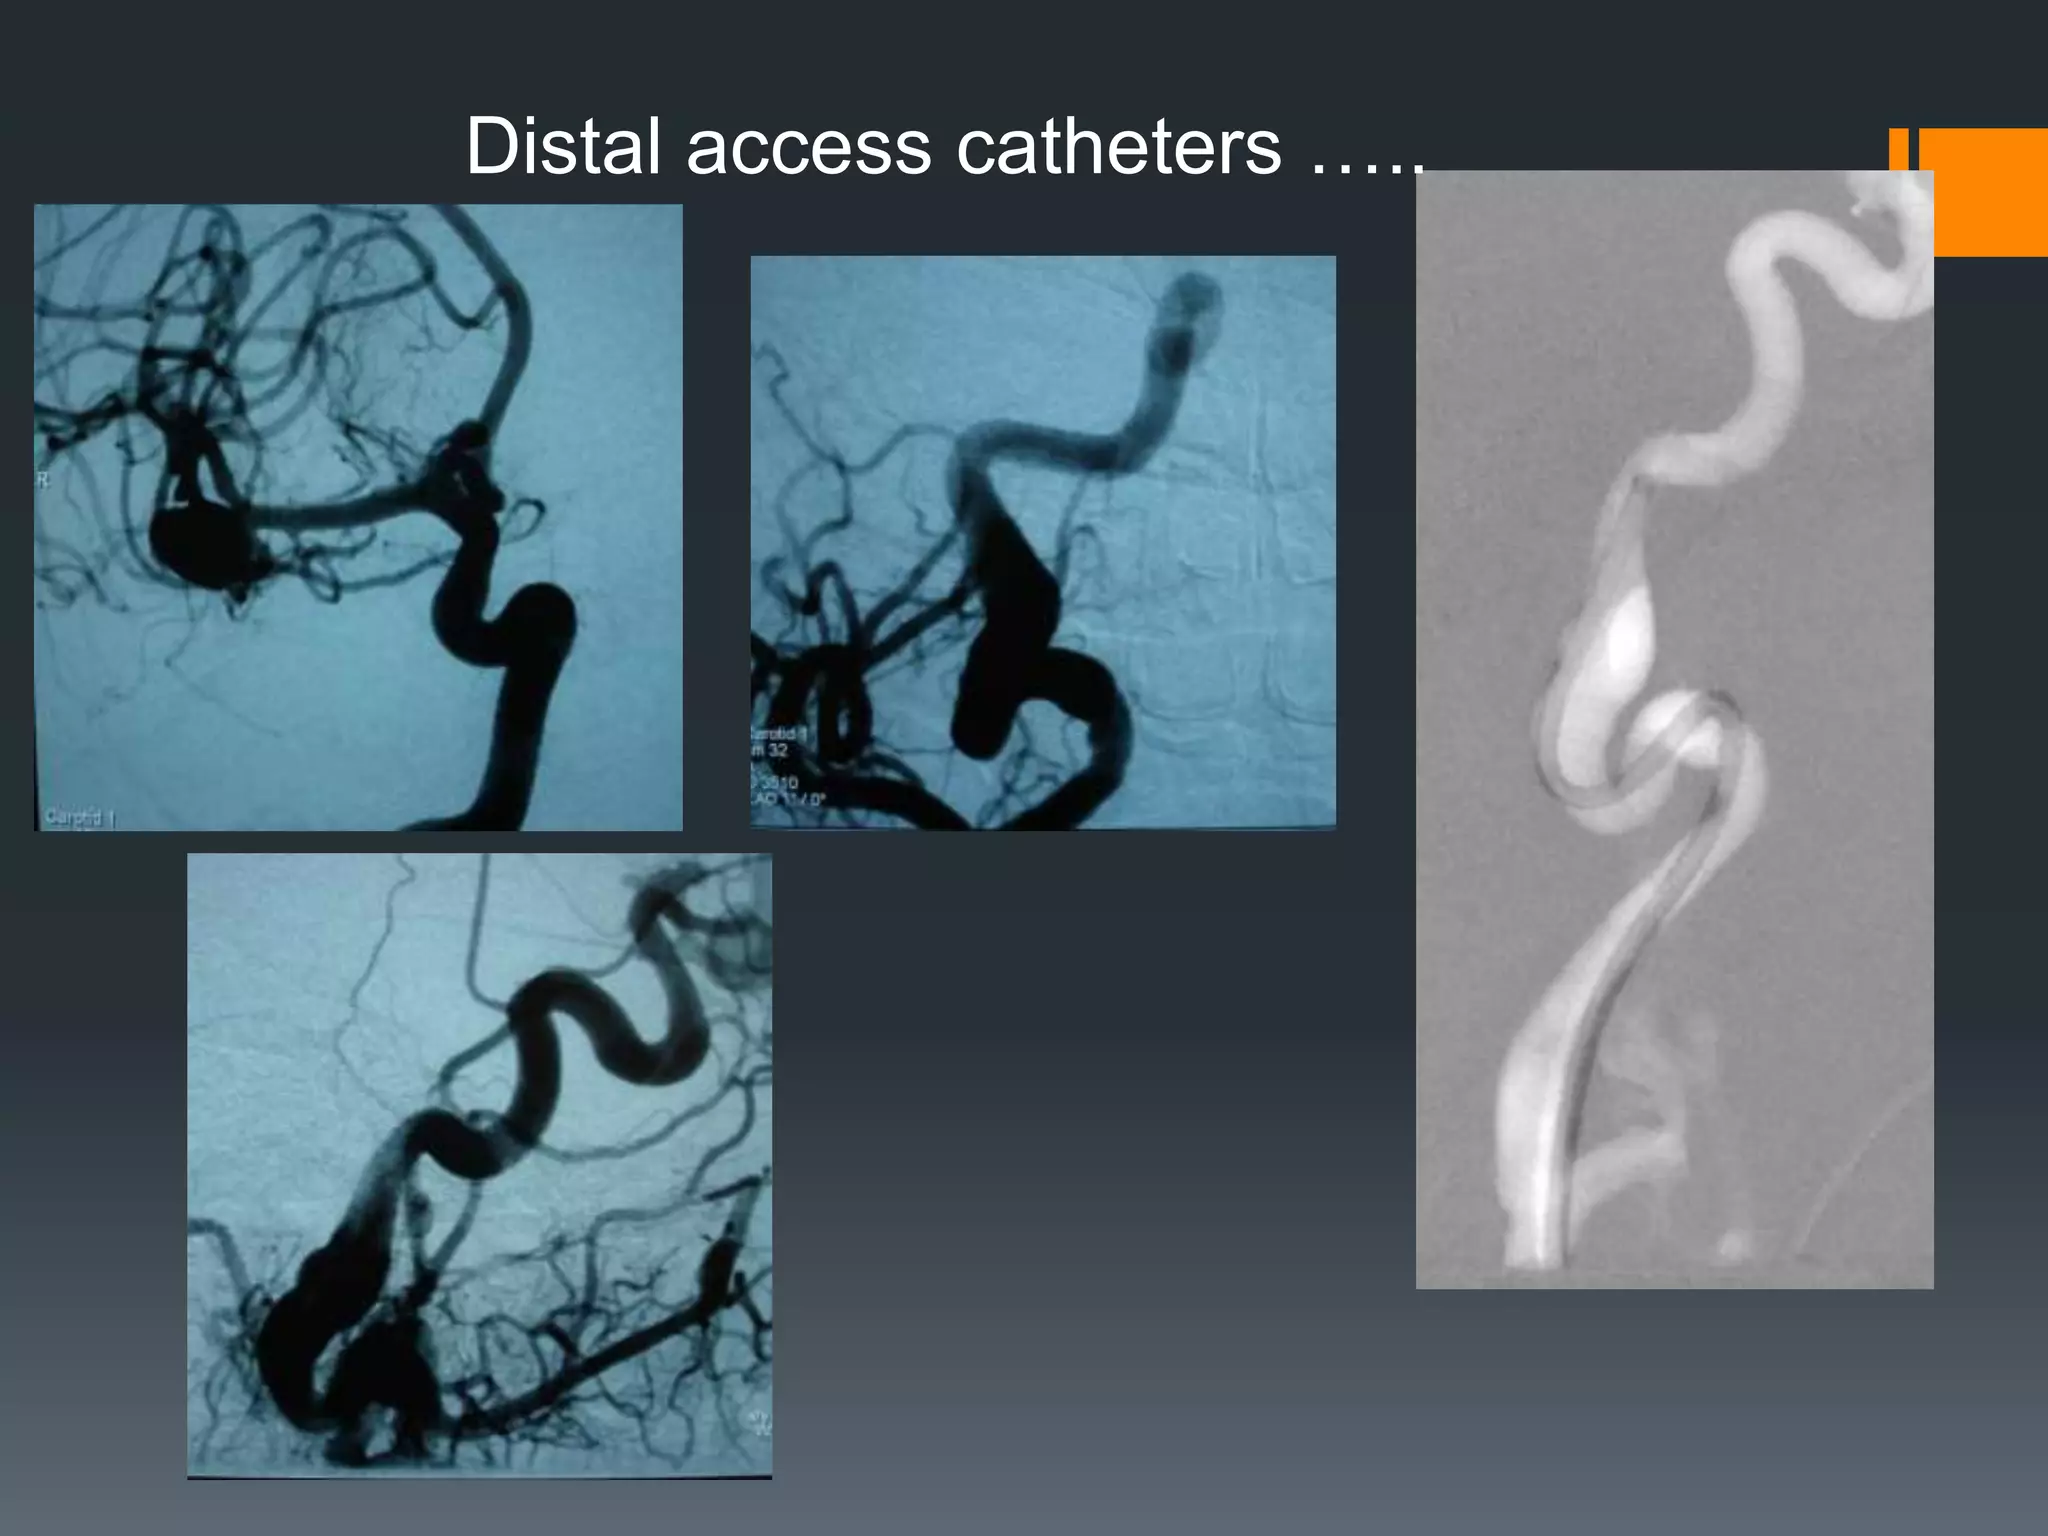

This document discusses tricks and techniques for difficult cannulations during neurointerventional procedures. It outlines strategies for accessing the aortic arch, internal carotid artery (ICA), and areas distal to aneurysms. Long sheaths, distal access catheters, and co-axial techniques are presented as options that have improved cannulation success. Guidance on sheath and catheter selection is provided for different vessel paths. The importance of catheter placement as high as possible in the ICA is emphasized. Reverse curve cannulations are also mentioned. Overall, the document stresses that careful cannulation is critical for procedural success and different strategies may be needed depending on the vessel target.